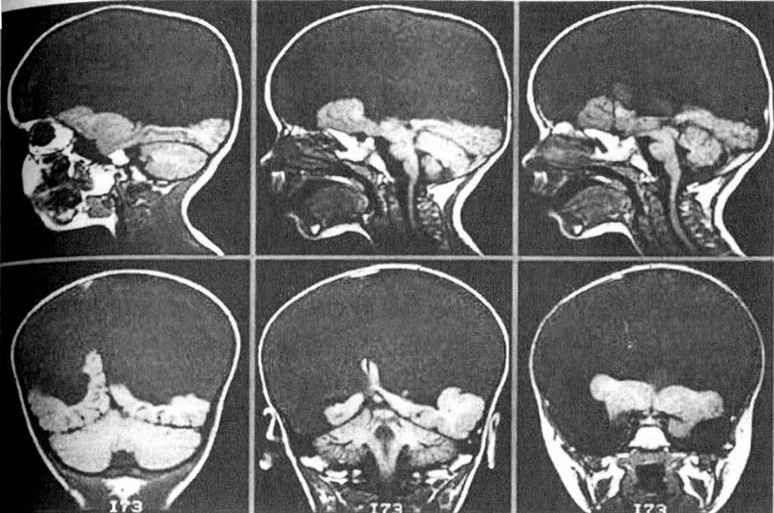

Магнитно-резонансные томограммы головы ребенка, страдающего гидроанэнцефалией. Большие полушария почти полностью отсутствуют, и вместо них череп заполнен спинномозговой жидкостью.

Одним из ярких свидетельств того, что сознание распространено гораздо шире, чем мы склонны признавать, может служить жизнеспособность и явная сознательность редких детей, рождающихся без коры больших полушарий головного мозга. Происходящий во время зародышевого развития микроинсульт или другая подобная аномалия может приводить к разрушению значительной части обоих больших полушарий. Неудивительно, что в результате дети появляются на свет с серьезными расстройствами, такими как плохое зрение или неспособность обучаться языку. Но при этом, как показал шведский нейробиолог Бьорн Меркер, некоторые из таких детей (несмотря на отсутствие у них почти всех отделов мозга, которые мы обычно связываем с сознанием) демонстрируют настоящее эмоциональное поведение, смеются и плачут, когда это уместно, и реагируют на окружающее вполне по-человечески. Я уже упоминал, что многие эмоциональные центры расположены у нас в древних отделах мозга, таких как мозговой ствол и средний мозг, похожие почти у всех позвоночных. С помощью магнитно-резонансной томографии Дерек Дентон показал, что именно эти древние структуры отвечают за такие базовые эмоции, как жажда или боязнь задохнуться. Вполне возможно, что корни сознания нужно искать вовсе не в “новомодной” коре больших полушарий (они, разумеется, вносят огромный вклад в сознание, однако лишь разрабатывают его на уже имеющейся основе), а в плотно структурированных древних отделах мозга, свойственных не только нам, но и широкому кругу других животных. А если так, то переход от нервных импульсов к чувствам неизбежно теряет часть окружающей его мистической ауры.